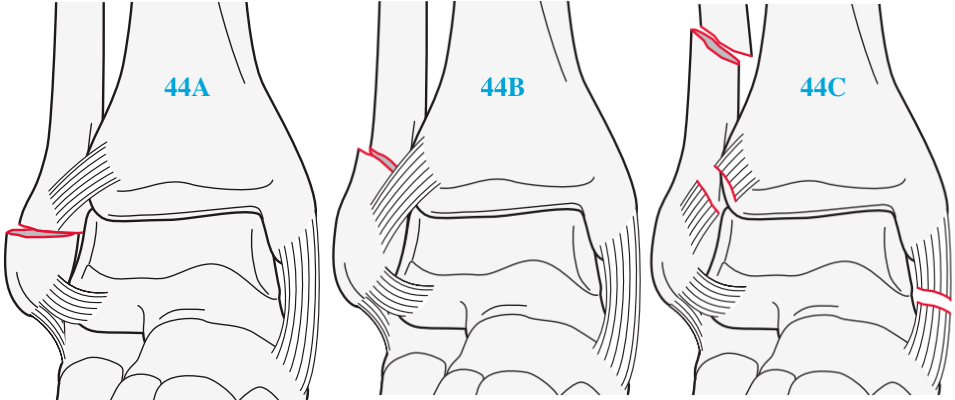

AO/OTA分型

首先以腓骨骨折线位置与远端胫腓联合之间的位置关系进行分类。该分型系统强调了外踝在踝关节稳定性中的重要性,易于使用,临床应用较广泛,对于手术中远端胫腓联合的修复有指导意义。

44A 腓骨骨折线位于下胫腓联合下方,下胫腓关节稳定;

44B 腓骨骨折线位于下胫腓联合平面,下胫腓关节稳定;

44C腓骨骨折线位于下胫腓联合上方,下胫腓关节不稳定。

AO分型中 A型损伤对应Lauge-Hansen分型中旋后内收损伤。

AO分型中 C型损伤对应Lauge-Hansen分型中旋前外旋损伤。